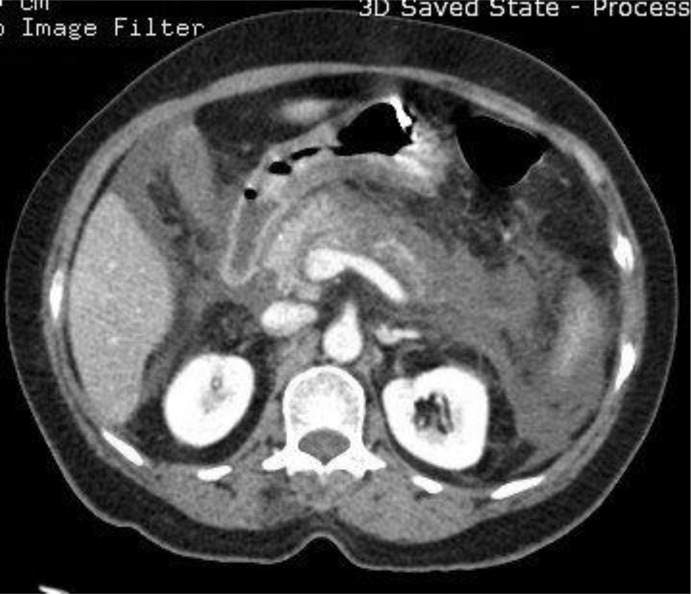

Acute pancreatitis is an exceptionally rare complication of scrub typhus. We report 2 cases of scrub typhus-associated acute pancreatitis from a tertiary care centre in Kolkata, India. The first case was a 27-year-old male patient, who presented in 2023, with severe epigastric pain a few days after the onset of fever. Laboratory investigations confirmed acute pancreatitis associated with scrub typhus. He had no additional organ involvement and recovered fully with intravenous doxycycline. The second case, reported in 2024, was a 42-year-old female patient who presented with fever, abdominal pain, vomiting and systemic complications, including acute kidney injury, hepatic dysfunction and pulmonary involvement. Despite the absence of eschar, investigations confirmed the diagnosis of scrub typhus. She achieved full recovery with doxycycline, haemodialysis and other supportive measures. Both cases emphasise the importance of considering scrub typhus in the differential diagnosis of acute pancreatitis in endemic regions, particularly when accompanied by febrile illness.